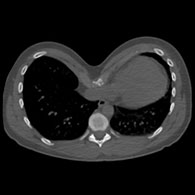

Indice di Haller

L'indice di Haller è stato istituito nel 1987 per valutare l'importanza di un Pectus sulla base di un calcolo effettuato su un'immagine digitale.

Viene stabilito tramite TAC nel punto più profondo della depressione: è il rapporto tra la larghezza e la profondità massima.

L'indice di Haller permette di misurare con maggiore precisione la profondità del petto escavato specialmente nelle donne, nelle quali la deformazione è difficile da valutare a causa del volume mammario. Quanto più l'indice di Haller è alto tanto più il Pectus Excavatum è profondo.

È pratico e ancora utilizzato, ma dà un'idea imperfetta dell'importanza della depressione e non pregiudica in alcun modo un possibile e raro impatto funzionale sul petto.